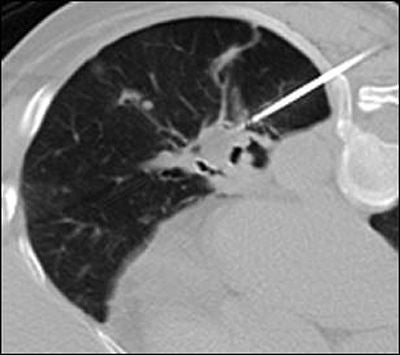

• Technical success for each treated tumour was defined as a zone of ground glass opacity, or visible ice encompassing the targeted tumour with at least a 5 mm circumferential ablative margin on CT at end of the cryoablation

• Cryoablation was performed applying a three-cycle freeze–thaw phase protocol